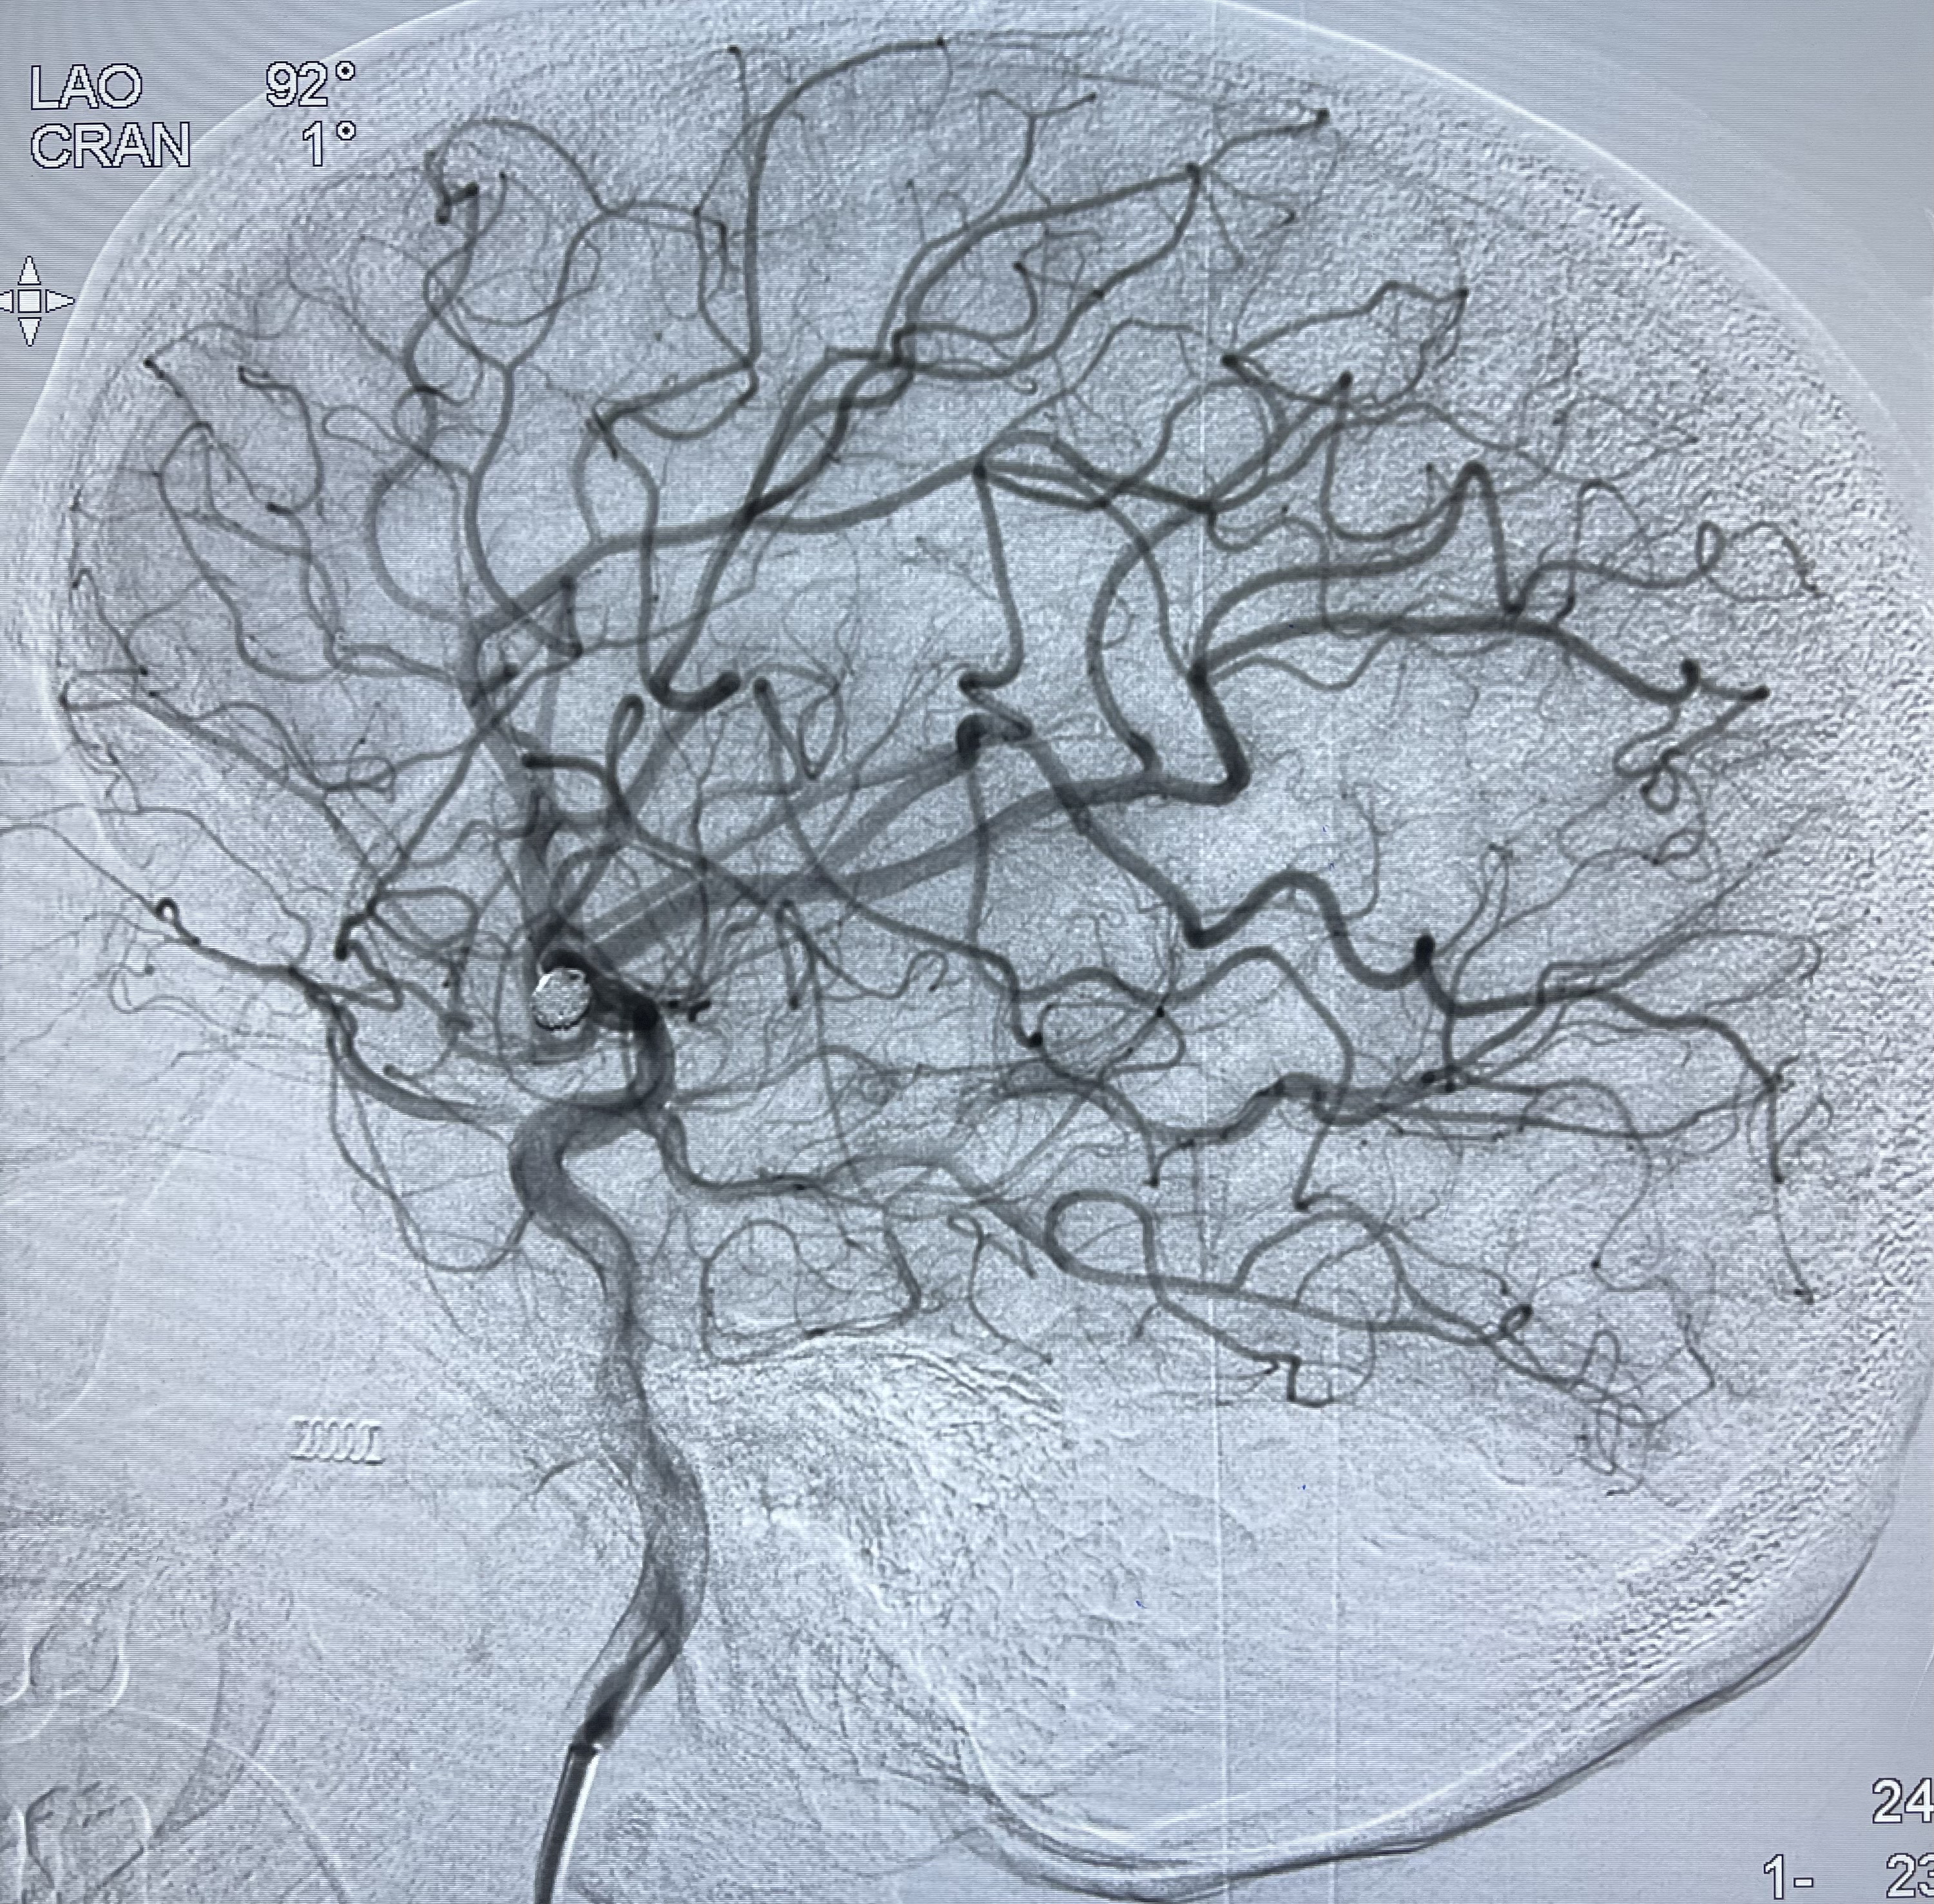

2021-01-11全麻下双微导管栓塞

工作角度显示瘤颈